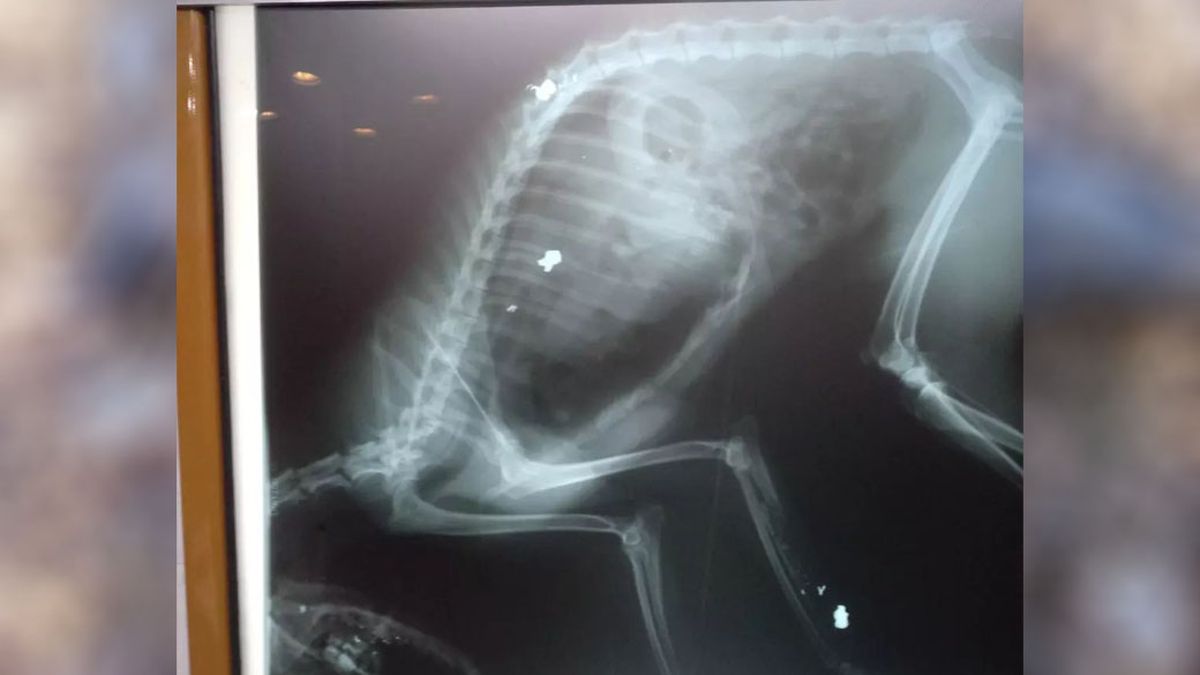

Se trata de un caso ocurrido el 17 de mayo del 2022 cuando Martín Díaz Durso le disparó cuatro veces con un aire comprimido a un zorro gris en la Avenida Los Cóndores, de El Salto, en Potrerillos. El animal era silvestre pero era conocido por todos los vecinos de la zona que lo habían llamado Juancho. Todos los días el animal pasaba por los jardines de las casas de esa zona, y era cuidado por todos.

El hombre fue denunciado en la Justicia por dos vecinos, uno de ellos testigo directo del momento en que Díaz Durso le disparó cuatro veces y el animal murió por las heridas causadas en el corazón, en la columna, en la mandíbula y en una pata.